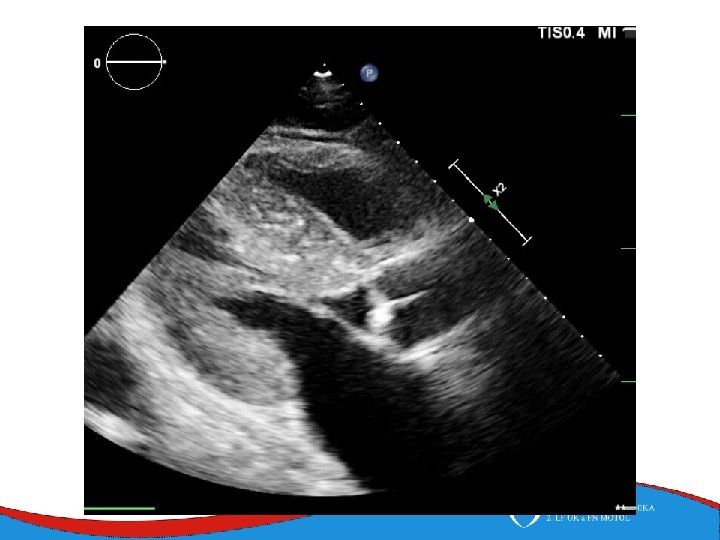

Restrictive cardiomyopathy Rare Mixed etiology Sarcomeric genes Restrictive physiology of diastolic filling Non-dilated ventricles, dilated atria

Symptoms Work- up Heart failure ECG Symptoms of underlying disease MRI ECHO Laboratory diagnosis of amyloid protein – free light chains, paraprotein Endomyocardial biopsy Scintigraphy – tnasthyretin amyloidosis